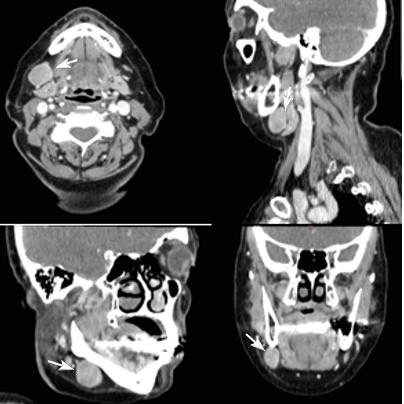

We present a woman at the age of 63 with a painless swelling in the right submandibular area with a discharge since three months. Of the examination, indirect laryngoscopy, mesopharygoscopy and nasopharyngoscopy does not establish a pathological finding. In the palpation of the neck in the right submandibular region there is an increased lymph node with a diameter of more than 3 cm. The CT with contrast diagnosed two suspected for metastatic lymph nodes in the right cervical area (Figure 1). After surgical excision of cervical lymph nodes, the biopsy proves metastasis from small cell anaplastic /neuroendocrine carcinoma. Immunohistochemical study reports: tumor cells express synaptophysine and CD56, focally positive to EМА and pancitokeratin, but negative to TTF1, S100 protein, CК 20 and CD45 (Figure 2 & Figure 3). The patient is judged to conduct 3 courses of chemotherapy (Ch), and then restaging. In April 2021, from a PET/CT data for a metabolic active lesion located right retromandibular, most likely a metastatic lymph node. Metabolic active hyleric and mediastinal lymph nodes are reported. [Figure 4].

Figure 1: CT with contrast visualized two lymph nodes in the right submandibular area, which are suspected for metastatic /marked with white arrows.

Extracutaneous origin of Merkel cell carcinoma- In the presence of a nodal Merkel cell tumor, an exhaustive clinicoradiologic search for a primary tumor must be carried out. After the exclusion of any reasonable starting point of the neoplasm, a provisional diagnosis of “primary” nodal Merkel cell carcinoma may be acceptable; since a primary extracutaneous tumor is expected to follow a less aggressive course than a metastatic one, follow-up data may provide indications as to the truly extracutaneous origin of MCC [28]. In the clinical case presented, the disease begins with increased retromandibular lymph nodes on the right (Figure 1), no primary cutaneous tumor or pathological lesion from the indirect laryngoscopy, mesopharingoscopy and nasopharyngoscopy.